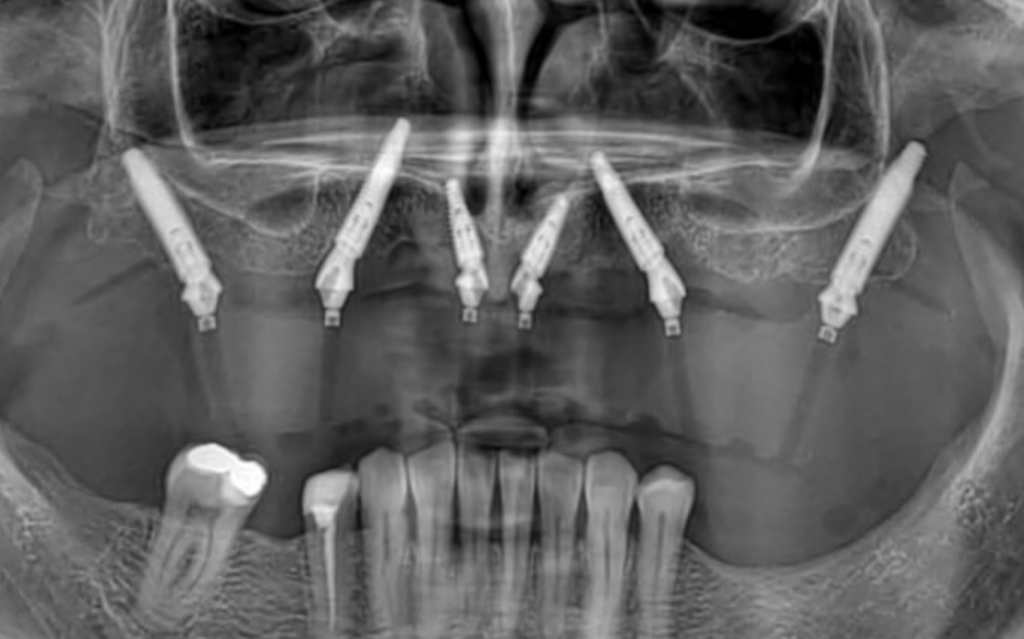

Rješenje potpune bezubosti, kao alternativa mobilnoj potpunoj protezi, su fiksni zubi na 4, 5 ili 6 implantata ovisno i kvaliteti kosti i funkcijskoj potrebi pojedinog pacijenta.

Standardni pristup je postavljanje četiri implantata u gornju i četiri implantata u donju čeljust (All-on-4) te izrada privremenih zuba unutar 24 sata od zahvata koji ostaju u pacijentovim ustima 6 mjeseci do potpune oseointegracije implantata nakon čega se izrađuje trajni most.

Trajni most se sastoji od titanske konstrukcije sa cirkonskim, kompozitnim ili akrilatnim zubima, ovisno o indikaciji.